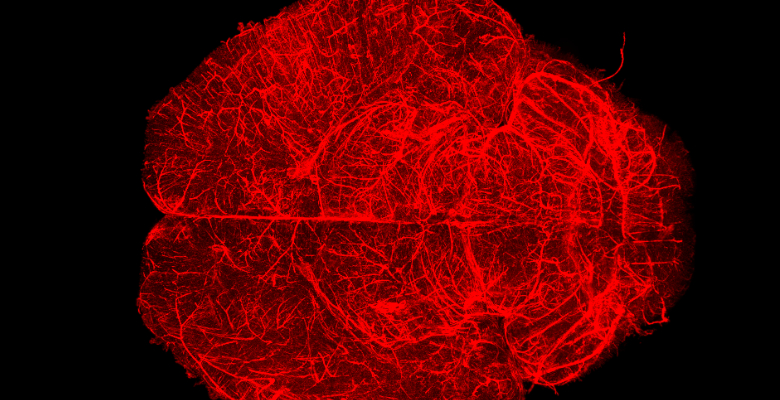

Investigadores da Universidade de Coimbra (UC) estão a estudar o cérebro de recém-nascidos para compreender de que forma o sexo biológico influencia o neurodesenvolvimento e a suscetibilidade a infeções. Este estudo parte de conclusões retiradas em estudos científicos anteriores.